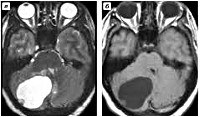

По макроскопическому строению в неврологии выделяют 3 группы гемангиобластом: солидные, кистозные и смешанные. Солидная (мягкотканная) гемангиобластома состоит из опухолевых клеток, собранных в единый окруженный капсулой узел, имеющий мягкую консистенцию и темно-вишневый цвет. Она составляет около 65% всех гемангиобластом. Кистозная гемангиобластома представляет собой гладкостенную кисту. В большинстве случаев на стенке кисты имеется небольшой солидный узелок. Примерно в 4-5% случаев встречаются гемангиобластомы смешанного типа, характеризующиеся наличием солидного узла, внутри которого расположены многочисленные кисты.

В большинстве случаев исследование послойных горизонтальных и сагиттальных срезов, полученных при проведении МРТ, позволяет установить локализацию опухолевого процесса и дифференцировать его от абсцесса головного мозга, внутримозговой гематомы, очага демиелинизации при рассеянном склерозе, последствий тяжелой черепно-мозговой травмы, кисты головного мозга Окончательная диагностика гемангиобластомы и определение ее микроскопического типа возможны лишь после гистологического изучения образца опухоли. Необходимые для исследования опухолевые ткани могут быть получены в результате стереотаксической биопсии мозга или в ходе операции по удалению опухоли.